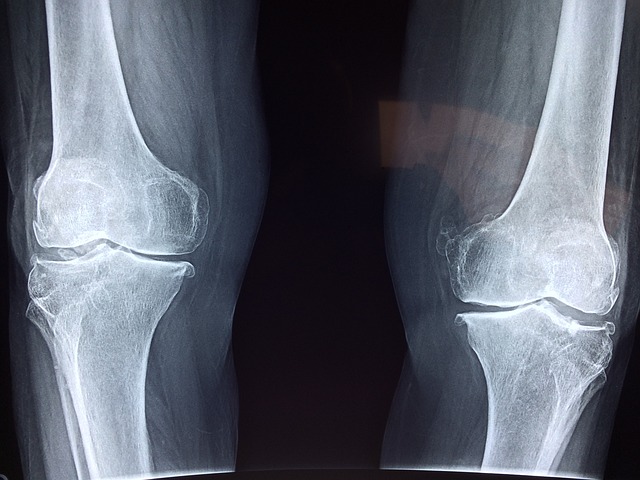

뼈는 우리 몸의 골격을 이루고, 전신을 지탱하며 움직임을 가능하게 하는 중요한 부분이에요. 나이가 들면서 골밀도가 점차 줄어들 수 있기 때문에, 뼈 건강을 유지하는 것이 중요하답니다. 오늘은 뼈를 튼튼하게 유지하는 데 도움이 되는 5가지 필수 영양소에 대해 알아볼게요. 균형 잡힌 식단을 통해 뼈 건강을 유지하는 방법을 소개해 드립니다!